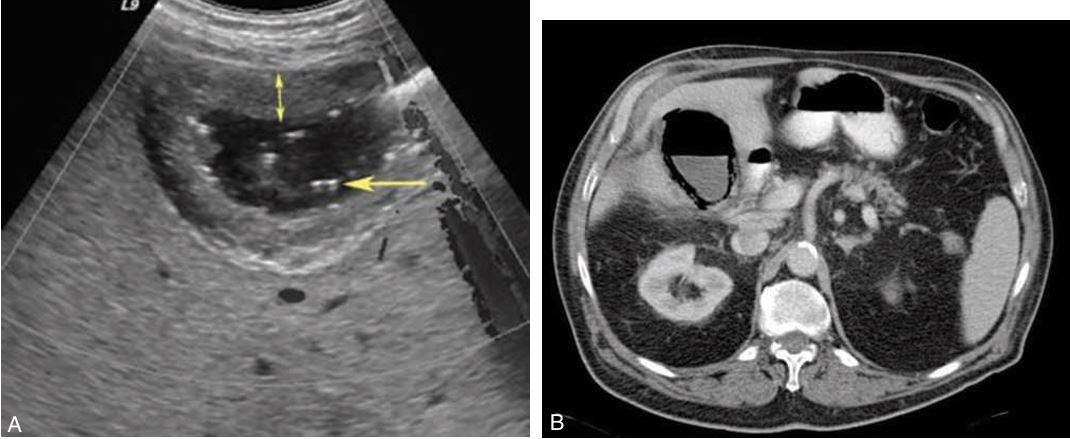

Emphysematous cholecystitis (showing ct scan too)

Carcinoma of the head of the pancreas with obstruction of the common bile duct (CBD) is demonstrated